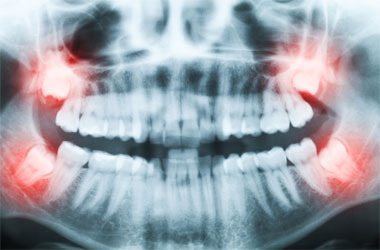

Patients suffering wisdom teeth pain or patients of an age where wisdom teeth may soon cause a problem can be evaluated at our office using a panoramic x-ray. The x-ray will clearly show the whole tooth (teeth) and allow us to determine the best treatment option for you.

Do you need wisdom teeth removal? Wisdom Teeth Removal is a common dental procedure for people in their late teens and early twenties. When wisdom teeth, or 3rd molars, do not erupt at all or only partially erupt, the patient has what is called “impacted” wisdom teeth. This condition often leads to pain or pressure on the adjacent teeth and a possible infection. Usually, the best treatment option is the extraction of the wisdom teeth.